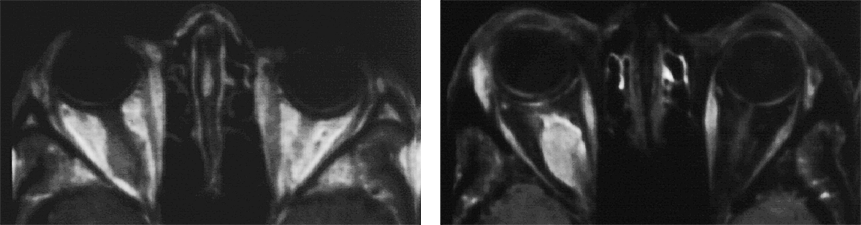

Figure 11-05:

Example of fat suppression — tumor in the right orbit. T1-weighted SE images.

Left: Plain image.

Right: Contrast enhancement of the tumor after gadolinium contrast agent. The tumor has become bright. The fat signal has been eliminated; both orbits now are dark and the enhancing parts of the tu­mor are easily delin­eated.